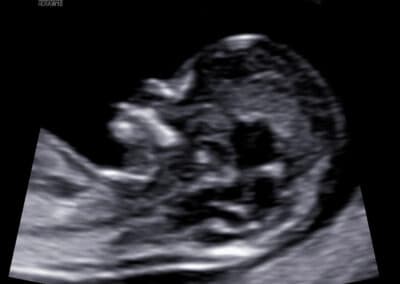

Vyšetření NT (šíjového projasnění)

věku maminky stáří budoucího miminka srdeční frekvence u miminka velikosti NT (nuchální translucence, respektive šíjového projasnění, což znamená, že změříme množství tekutiny nahromaděné v podkoží v oblasti šíje miminka) koncentrace dvou hormonů v krvi maminky (free-ß-hCG & PAPP-A)

věku maminky stáří budoucího miminka srdeční frekvence u miminka velikosti NT (nuchální translucence, respektive šíjového projasnění, tzn. znamená změření množství tekutiny nahromaděné v podkoží v oblasti šíje miminka) (velikost „nuchální translucence“) koncentraci dvou hormonů v krvi maminky (free-ß-hCG & PAPP-A) přítomnosti/chybění nosní kůstky plodu normálního nebo abnormálního průtoku krve (výskytu trikuspidální regurgitace) na trojcípé srdeční chlopni miminka normálního nebo abnormálního průtoku (zvýšené hodnoty PI, tzn. indexu pulzatility) v ductus venosus miminka